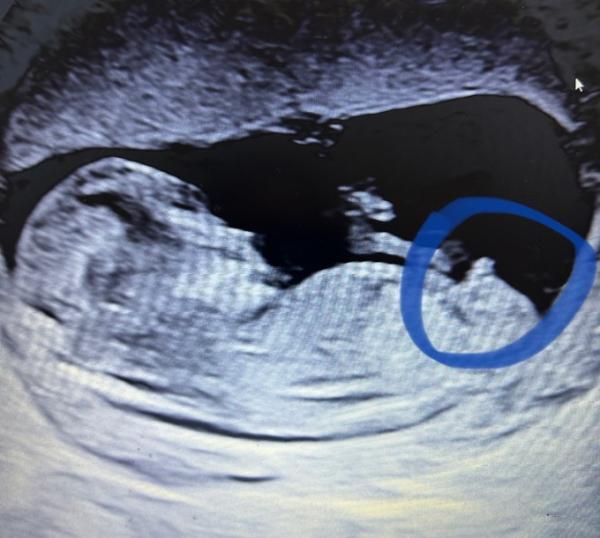

Hallöchen, ich war vorhin beim Ersttrimester-Screening. Alles war super unauffällig und die Ärztin war sehr zufrieden. Wir haben ganz viele Fotos mitbekommen und es gab schon eine erste Tendenz welches Geschlecht das Baby hat Euch noch einen schönen Tag!

Bild zu Ersttrimester-Screening - Forum für November - Mamis

Herzlichen Glückwunsch Mädchen, oder ? Alles Liebe für euch!

Danke! :) Ja tatsächlich ist die Tendenz Mädchen. Erkennt man das auf dem Bild? Die Pränataldiagnostikerin meinte, dass man es wohl Anhand des Beckens des Babys unterscheiden kann. Ich hab da ehrlich gesagt nichts erkannt!

ja ich zeig dir mal mein Bild von der Nackenfaltenmessung- mir wurde gesagt es wird ein Junge weil das da vorne so aufsteht & bei Mädchen sind so Waagrechte striche wie auf deinem Bild ich glaub das ist die sogenannte NUB Theorie! Aber die werden sich schon auskennen